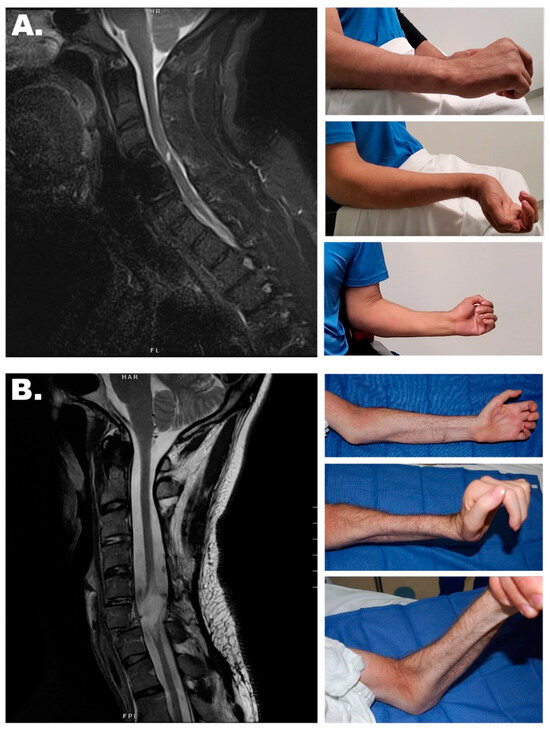

3.1. Nerve Transfers

- Bazarek, S.; Sten, M.; Thum, J.; Mandeville, R.; Magee, G.; Brown, J.M. Supinator to Posterior Interosseous Nerve Transfer for Recovery of Hand Opening in the Tetraplegic Patient: A Case Series. Neurosurgery 2024, 94, 1253–1261. [Google Scholar] [CrossRef] [PubMed]

- Bazarek, S.; Sten, M.; Nin, D.; Brown, J.M. Supinator to Posterior Interosseous Nerve Transfer for Restoration of Finger Extension. Oper. Neurosurg. 2021, 21, E408–E413. [Google Scholar] [CrossRef]